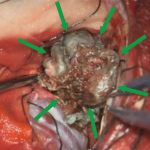

手術写真

手術中

手術の結果

(画像クリックで拡大できます)